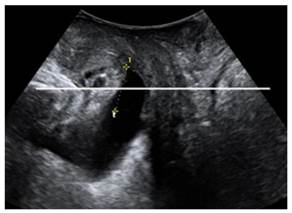

Two-dimensional (2D) ultrasound were used to determine pelvic organ prolapse in midsagittal plane on maximal Valsalva maneuver (best of at least three maneuvers)[19]. The inferiorposterior margin of the symphysis pubis serves as a line of reference. On maximum Valsalva, the maximum descent of the bladder, the cervix or vaginal vault, the cul, the sac and rectum were determined relative to the reference line. In normal condition, the leading edge of pelvic organs was above the reference line; otherwise, it was defined as pelvic organ prolapse.

Figure 4

Two dimensional ultrasound imaging showing cystocele.

The levator hiatal dimensions were significantly larger in the postpartum female than that in normal nulliparas, with an oval or circle shape. On TUI, avulsion of the puborectalis muscle was detected in eight cases among those delivered vaginally on maximum pelvic floor contraction (Fig. 3), including 4 unilateral avulsion (2 cases of full avulsion and 2 of partial avulsion) and 4 bilateral avulsion (1 case of bilateral full avulsion and 1 case of left-sided full avulsion and right-sided partial avulsion, and 2 cases of right-sided full avulsion and left-sided partial avulsion). No such defects were observed in Cesarean section group. Pelvic organ prolapse was detected on maximum Valsalva. Twelve cases displayed cystocele including 10 from Vaginal delivery group and two from Cesarean section group (Fig. 4). In the axial plane, the arrangement of urethra, vagina and rectum changed, and bladder was also detected in levator hiatus.

The incidence of pelvic organ prolapse (21.28% vs. 4.17%) and pubrectalis muscle avulsion (17.02% vs. 0%) was significantly higher in Vaginal delivery group compared to Cesarean section group (P<0.05).